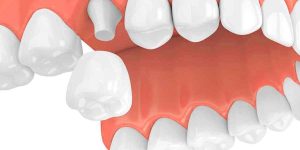

Periodontal Disease – You Might Have it and Not Even Know It

The majority of people have some level of periodontal disease. A milder form of gum disease is called gingivitis and as it becomes more serious it becomes periodontitis. Most people don’t even know that they have it and go on with their lives while the condition gets worse and worse. And, even if someone is aware that they have some form of periodontal disease, they usually procrastinate visiting a dentist, because they don’t feel any pain. If you want to keep your teeth for life, you need to go to a good dentist Brooklyn on a regular basis to maintain the healthiest teeth and gums. What Are Some Signs That Might Indicate You Have Periodontal Disease? • Swollen, tender or